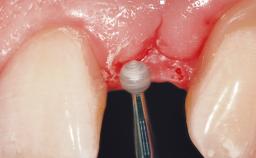

Early Placement of an Implant in a Maxillary Right Central Incisor Site

This 41-year-old female patient was referred to the clinic for the replacement of the right central incisor, since the tooth had developed a root fracture in the long axis that made extraction necessary. The healthy, non-smoking patient was first seen with the tooth still in place. A detailed Esthetic Risk Assessment was performed.The patient was worried about her dental esthetics and had high expectations for a successful treatment outcome from an esthetic point of view. The patient had a medium lip line that displayed parts of the gingiva in the anterior maxilla upon smile.

Abutment Type Customized

Prosthesis Type FDP

Provisional Implant-Supported Prosthesis Prosthodontic margin < 3 mm apical to mucosal margin Prosthodontic margin < 3 mm apical to mucosal margin

Interim Prosthesis during Healing Removable Removable